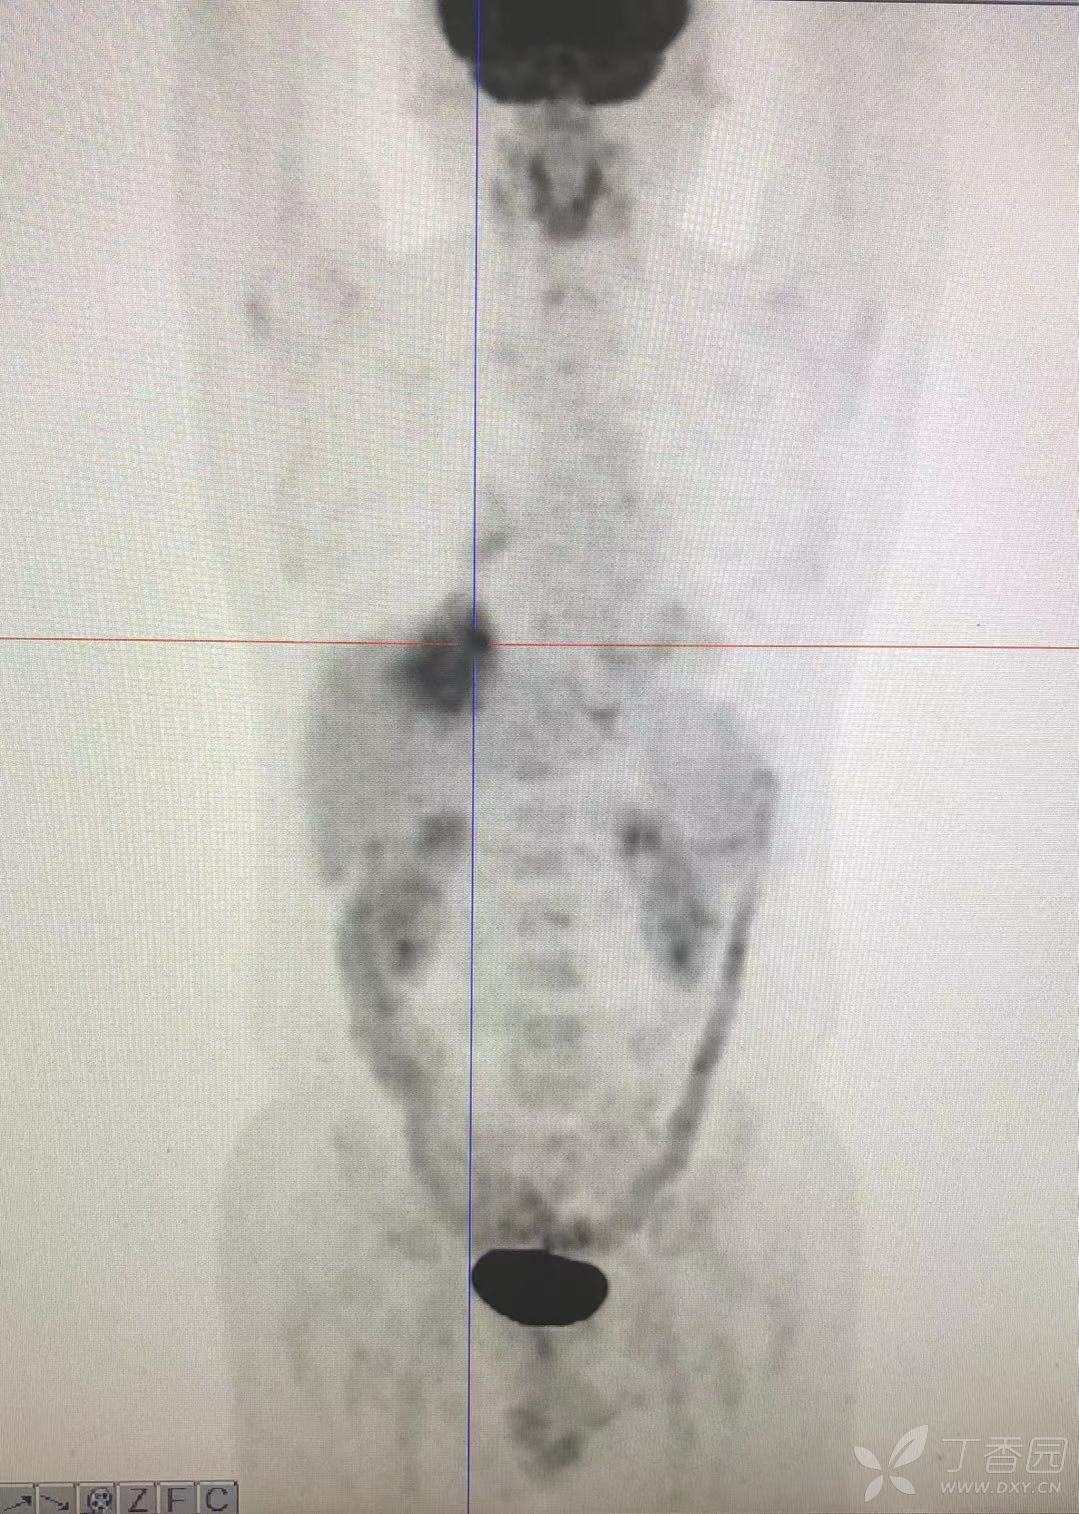

简要病史:咳嗽、咳痰,体重减轻5Kg+。

辅助检查:CT提示:右下肺占位伴周围炎症,CA待排,右侧少许胸腔积液。

临床诊断:右肺癌?待进一步检查。